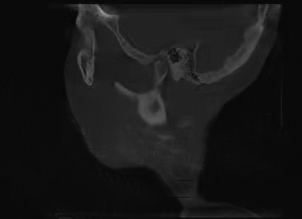

颞下颌关节由关节窝、髁突、关节盘及其周围软组织构成。髁突位于关节窝内,关节盘将髁突与关节窝分割为上下两个间隙,以避免骨性凹陷与髁突直接接触造成损伤。一般来说,髁突在关节窝中的矢状向位置关系更容易受到咬合闭合道及闭口位的影响,从而建立不良的关节结构关系,把关节盘挤出关节窝,造成髁突与关节窝之间的直接接触,损伤髁突。 髁突在关节窝中处于什么样的生理位置才有利于关节的功能运动及咬合,评价标准一直不统一。 近年来,更多的研究结果证实,在关节结构正常的条件下,牙尖交错位时的髁突在矢状向上基本处于居中的位置,即前后间隙甚至包括上间隙基本相等,这可以作为关节结构分析的参考。同时,牙尖交错位时,关节结构及其周围肌群甚至牙周状态均是协调舒适的,下颌运动时所有结构在这个过程中是轻便无障碍的。然而,这些理论均是建立在关节结构没有损伤的前提下,一旦结构发生损伤,比如髁突吸收,很难找到一个可量化的标准,理想的量化标准只能作为参考。 对于损伤后的关节,如何定位和评价其结构是否合理,目前没有相关概念和指标进行描述。理论上认为,颞下颌关节结构正常时,髁突在关节窝中的位置居中;已经损伤的髁突在关节窝中应有一定的修复空间,无论关节盘处于什么样的状态,只要在临床上患者没有任何不适且下颌功能正常,并经过一定时间的观察发现预后良好,就可以定义为关节舒适位。“舒适的”不一定全是形态健康完整的,损伤后的结构在舒服的环境中有可能慢慢修复;在不舒服的环境中,健康无从谈起。截至目前,还没有公认的关于关节结构,尤其是髁突位置和关节盘状态准确的、定论性的统一标准,也没有关于关节功能紊乱患者的治疗评价标准。

对咬合异常患者要进行临床检查、面型分析、影像学检查等,然后对结果进行综合分析。临床面诊是第一位的,不仅可以看到患者静态的一般情况、面部和咬合特征,还可以观察到患者包括肌位、牙位状况在内的咬合运动、语言、呼吸、发音等功能特征。动态观察一定不可忽略。 除此之外,基于功能运动的咬合分析,对关节病患者使用什么仪器和检查方法,要根据具体情况选择。比如,对下颌各种运动形式的各种检查,可以观察到下颌的运动状态及牙齿尖窝接触点的情况,用来分析咬合是否有碍关节结构和功能的敏感点。具体的方法包括观察法、手诊法、咬合纸检查、T-Scan(T-扫描)动态咬合力检查、髁突运动轨迹描记、头影测量、夜磨牙片、牙尖斜度测量、锥形束CT检查、MRI(磁共振)检查等。 需要注意的是,所有的测量方法都有侧重,医生可以根据实际需要选择一种或几种方法。 一般来说,应用单一的方法难以准确地发现问题;几种方法联合应用,相互印证,相互补充,能让医生更加全面地分析是否存在不足或不正确。但是,对于致力于咬合病治疗的专业人士,掌握头影测量、锥形束CT和MRI的检查方法、制取与分析很有必要,这些也是比较基本的技能;否则,很难做出一个完整、系统、科学的治疗方案。